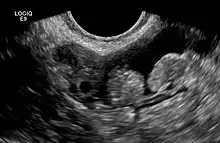

2 epiploic appendages next to an ovary in pelvic ultrasound

The epiploic appendices (or appendices epiploicae, or epiploic appendages, or appendix epiploica, or omental appendices) are small pouches of the peritoneum filled with fat and situated along the colon, but are absent in the rectum.

They are chiefly appended to the transverse and sigmoid parts of the colon, however, their function is unknown.